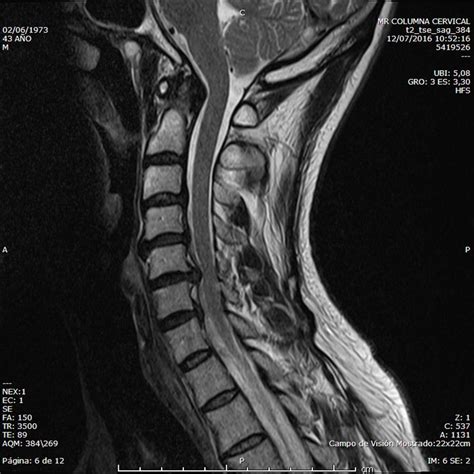

- Resonancia Magnética (RM): Es la prueba de elección para delimitar la anatomía vertebral, el líquido cefalorraquídeo, la compresión medular o radicular y los tejidos blandos. Se indica en casos de sospecha de lesión tumoral o infecciosa, o cuando el tratamiento inicial fracasa.